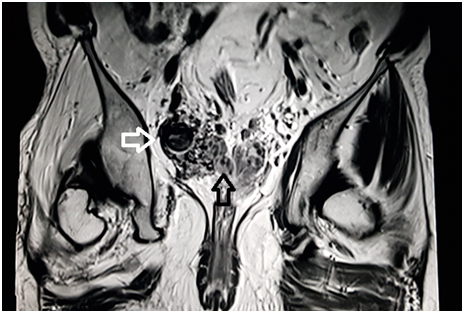

A 39 year old male presented with the chief complaint of pelvic discomfort and on and off haematuria. It was not associated with fever or urinary retention. No bowel symptoms were noted. Patient had history of paralytic poliomyelitis in his childhood and walked with crutches. On laboratory examination, patient was found to have deranged renal function tests with elevated creatinine level. Hence, we conducted MRI pelvis with MR urography to look for the urinary systemand to look for the status of the the pelvic muscles and joints. MR study showed multiple tortuous dilated vessels on the right side of pelvis suggestive of pelvic arteriovenous malformation (Figure 1&2). The arterial supply was noted from multiple branches of the right internal iliac artery and venous drainage was noted into right external iliac vein and deep external pudendal vein. The tangle of vessels was abutting the right lateral wall of urinary bladder, prostate and right seminal vesicle medially (Figure 1&3). It was abutting the obturatorinternus muscle laterally. There wasasymmetric thickening of the right lateral wall of urinary bladder adjacent to the vascular malformation (Figure 1). It was not associated with perivesicular fat strandings or enlarged locoregional lymphnodes. No restriction of diffusion was noted in DWI images. Prostate and bilateral bilateral seminal vesicles were normal in signal intensity and morphology. As a sequalae of childhood poliomyelitis, diffuse atrophy of pelvic muscles was noted that was more prominent on the right side (Figure 4&5). T1 and T2 high signal intensity suggestive of fatty replacement was noted in bilateral psoas and right obturaterinternus mucle. Fatty atrophy of bilateral hip and proximal thigh muscles were also seen (Figure 5). Abduction and external rotation was noted at bilateral hip joints (Figure 4). Histological examination of the bladder wall revealed polypoid bladder mucosa with chronic inflammation consistent with polypoid cystitis. Arteriovenous malformation was managed with intra-arterial coil embolization and subsequently the patient’s symptoms improved.

Figure 4 MRI axial T2 weighted image through the lower pelvis demonstrate diffuse fatty atrophy of the gluteal muscles (black arrows) that is more prominent on the right side. Marked fatty atrophy of right obturatorinternus muscle is also noted (white arrow). External rotation of bilateral hip joint is demonstrated. These findings represent sequalae of childhood paralytic poliomyelitis.

Figure 5 MRI coronal T1 weighted image through the gluteal region demonstrate diffuse fatty atrophy of the gluteal muscles (black arrows) that is more prominent on the right side. It occurred as a sequalae of paralytic poliomyelitis.